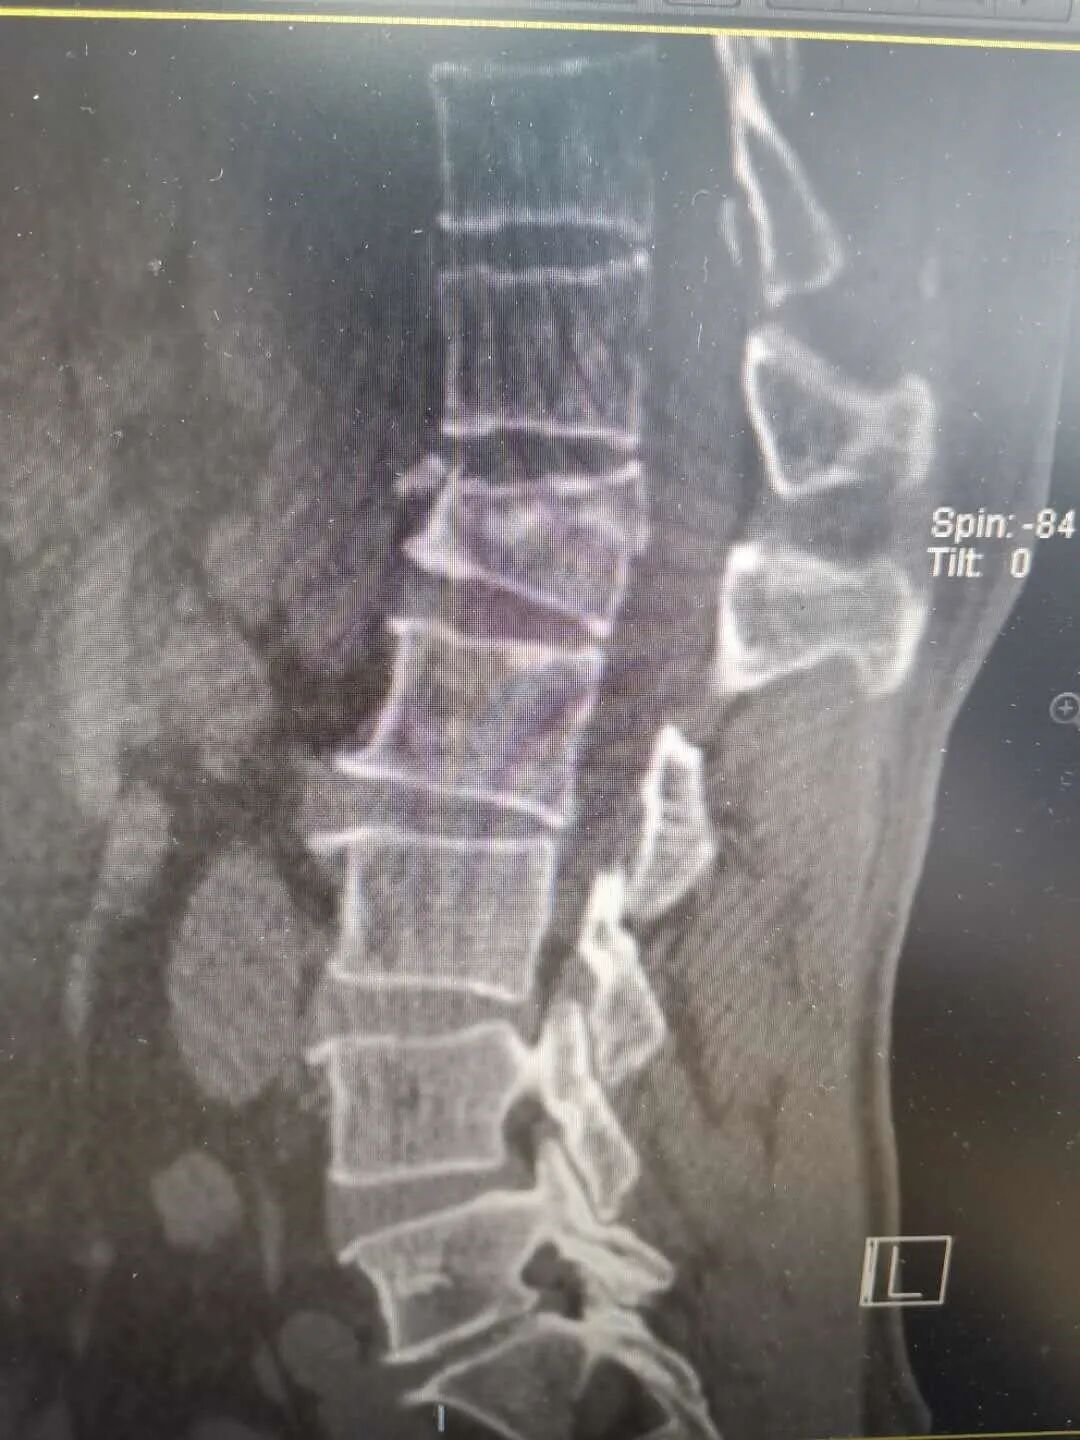

54岁的丁先生,在工地干活时不慎从2米高的高处坠落,臀部着地,当时丁先生只觉得腰部剧痛,不能自如活动,随即由工友送到了海宁康华医院骨2科就诊。 经过CT检查,发现丁先生腰1椎骨折,压缩了约1/2,需要立即采取手术。 丁先生考虑到自己是家中重要的劳动力,强烈要求采取创伤小、恢复快的方案进行治疗,以便自己尽快恢复工作。骨2科团队经过认真研究,决定采用微创小切口的方式在脊柱后路用钉棒固定丁先生因骨折压缩的腰1椎体。最终手术顺利完成。 术后经过复查,CT图像提示腰椎高度回复,内固定位置良好,一周后即可下床。 康华医院骨2科主任、副主任医师陈杰介绍,传统处理腰椎骨折手术需要切开皮肤,剥离肌肉,显露椎体结构后,植入椎弓根螺钉固定,存在切口长、椎旁肌肉剥离广泛、术中出血多、术后切口引流量大、术后切口疼痛、恢复期长等一系列的问题。 而像丁先生这样采取经皮微创植入椎弓根钉棒固定的手术,因其手术创口小(约1cm*6),术中出血少,不剥离椎旁肌肉,术后切口无需引流,无术后切口疼痛,可早期下地进行功能恢复,是近年来发展起来一项技术,也是近年来治疗腰椎滑脱、胸腰椎骨折、椎管狭窄等脊柱疾病采用的一种手术方式。 因为是微创技术,对手术技术要求比传统手术方式更高,术前需要非常周密的计划,根据患者的影像资料做非常精确地测量和定位,更需要手术医生具有非常娴熟技术,因此之前只有一些三甲大医院才有开展。近年来,骨2科在陈杰主任带领下,刻苦钻研,不懈追求,不断精进,希望能以更精湛的技术,温馨的服务,竭力为广大患者解除病痛。